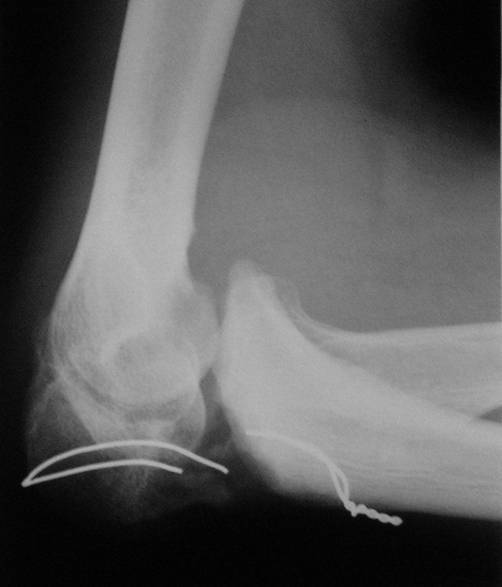

Уважаемые коллеги! Пациент 34 лет. Человек физического труда. Восемь месяцев назад в отделение сочетанной травмы был произведен остеосинтез локтевого отростка проволокой. В последующем r занимался разработкой сустава. Когда понял, что восстановить сустав не удастся, обратился за помощью. Предполагает, что после операции функция сустава восстановится полностью. Мы думаем выполнить операцию в два этапа: 1. Первый этап - аппаратом вправить предплечье 2. Второй этап - остеосинтез локтевого отростка спонгиозным винтом, или пластиной, или по Веберу с костной аутопластикой.Помогите советом. С уважением Н.Петров

По представленному снимку можно сделать заключение не только о несостоятельности МОС и технических погрешностях, допущенных при его наложении, но сейчас ГЛАВНЫЙ вопрос равномерного лизиса отростка. Он прозрачен на снимке, а значит лишен питания (частично или полностью - это Вам надо выяснить!). Следовательно можно думать о аваскулярнои некрозе л.отростка, следовательно - костная аутопластика необходима, но какая? Я думаю только несвободная, обязательно на сосудистой ножке, или если свободная, то с включением питающего трансплантат сосуда в одну из возвратных артерий локтевого сустава.